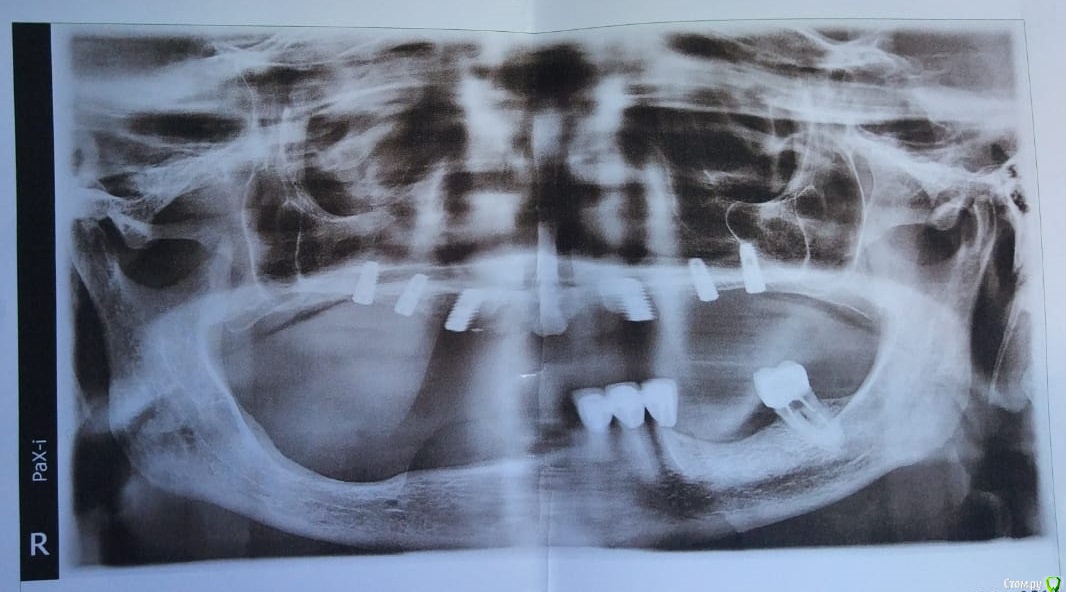

rimtar Опубликовано 18 августа, 2019 Поделиться Опубликовано 18 августа, 2019 (изменено) Имеем пациентку 73 лет, после открытых синусов\расщепления поставил 6 имплантов. в области шестых- 4.0*10 и 4.0*8.5, остальные 3.5*8.5. хотел на балке съемный, но пациентка очень настойчиво просит несъемный. допустимо?благодарен за любой совет\комментарий Изменено 18 августа, 2019 пользователем rimtar Ссылка на комментарий

chervoncevdaniil Опубликовано 18 августа, 2019 Поделиться Опубликовано 18 августа, 2019 (изменено) 6 имплантов в том положении который вы поставили и протез на балке?Как вы себе такую балку представляете?И почему раз балку вы ставите 6 имплантов,хотя 4,максимум 5 в переднем отделе заглаза?По поводу несъемного,что там с поддержкой мягких тканей,судя по ОПТГ там навряд ли несъемная консрукция пройдет.Вообще интересно,почему после имплантации пациентка просит несъем,хотя вы планировали съем? Изменено 18 августа, 2019 пользователем chervoncevdaniil Ссылка на комментарий

Дмитрий Л. Опубликовано 18 августа, 2019 Поделиться Опубликовано 18 августа, 2019 По оптг невозможно судить о параллельности имплантов. Если у вас есть возможность запротезировать на стандартных абатментах мк подковой - было бы супер. Пускай это будет хоть и цементная. Если нет - то либо мультиюоиты, либо индивидуальные. Вопросы только к оголившимся виткам резьбы. 1 Ссылка на комментарий

pit Опубликовано 30 августа, 2019 Поделиться Опубликовано 30 августа, 2019 Все очень просто, когда знаешь, что делаешь)Как поступить в данном случае, что бы определиться с видом протеза?Надо открыть имплантаты, сделать оттиск с трансфер-чеком, определить и зарегистрировать центральное соотношение и сделать примерку прототипа несъемной конструкции на имплантах.На прототипе оценить:1. Визуализацию границы протеза и десны. Линию улыбки2. Поддержку верхней губы3. Выход шахт имплантатов4. Продемонстрировать пациенту внешний вид конструкцииИнтерпретация оценки. Пункты 1,2,4 определяют съемная или несъемная будет конструкция. Пункт 3 определяет тип фиксации, если будет несъемная конструкция. 4 Ссылка на комментарий

Kotyara Опубликовано 1 сентября, 2019 Поделиться Опубликовано 1 сентября, 2019 судя по атрофии, все мягкие ткани будут уже на самом протезе. и соответственно эстетику лица можно делать за счет него. Поставьте мульти юниты и делайте то, за что она готова заплатить 1 Ссылка на комментарий